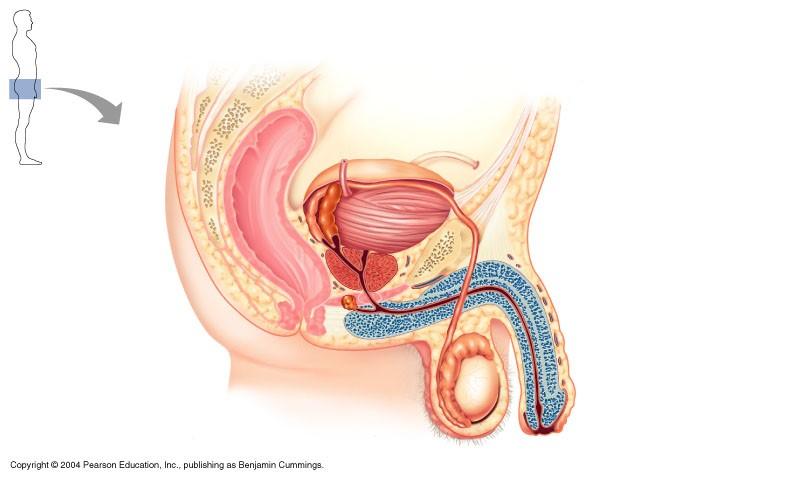

The structure indicated in the diagram of male reproductive system is

Vas deferens

Which is the most correct sequence of sperm flow in the male duct system

seminiferous tubules, epididymis, vas deferens, ampulla, ejaculatory duct, urethra

The structure indicated in the diagram below of the male reproductive system is

epididymis

The structure indicated in the diagram of the male reproductive system is the ejaculatory duct

The structure indicated in the diagram of male reproductive system is epididymis

tissue surrounding male urethra

corpus spongiosum

erectile tissue in male penis

corpus carvenosum

Male reproductive system

ampulla of ductus deferens

vas deferens

prostate

epididymis

testes

male reproductive structure